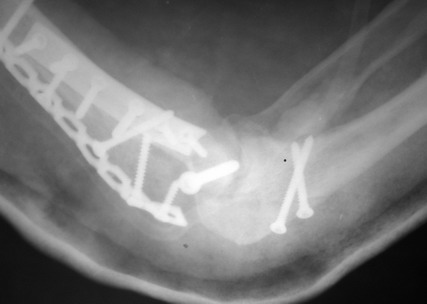

Женщина 42 лет, операция через неделю после перелома.

Д-з - открытый перелом мыщелков со смещзением и локтевой кости

без смещения - падение с лошади.

До операции снимки не очень, тем более в гипсе.

Остеосинтез закрытый (если так можно выразиться), т.е. без

разрезов. Длительность операции - около 1,5 часа со студентом.

6 щелчков ЭОПом.